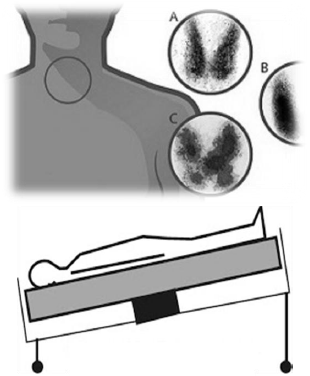

- Protocolos de Exames de Medicina NuclearBases Físicas e Tecnológicas

- Protocolos de Exames de Medicina NuclearTécnicas Radiográficas em Tomografia Computadorizada

A partir da análise das imagens abaixo escolha a única alternativa correta: